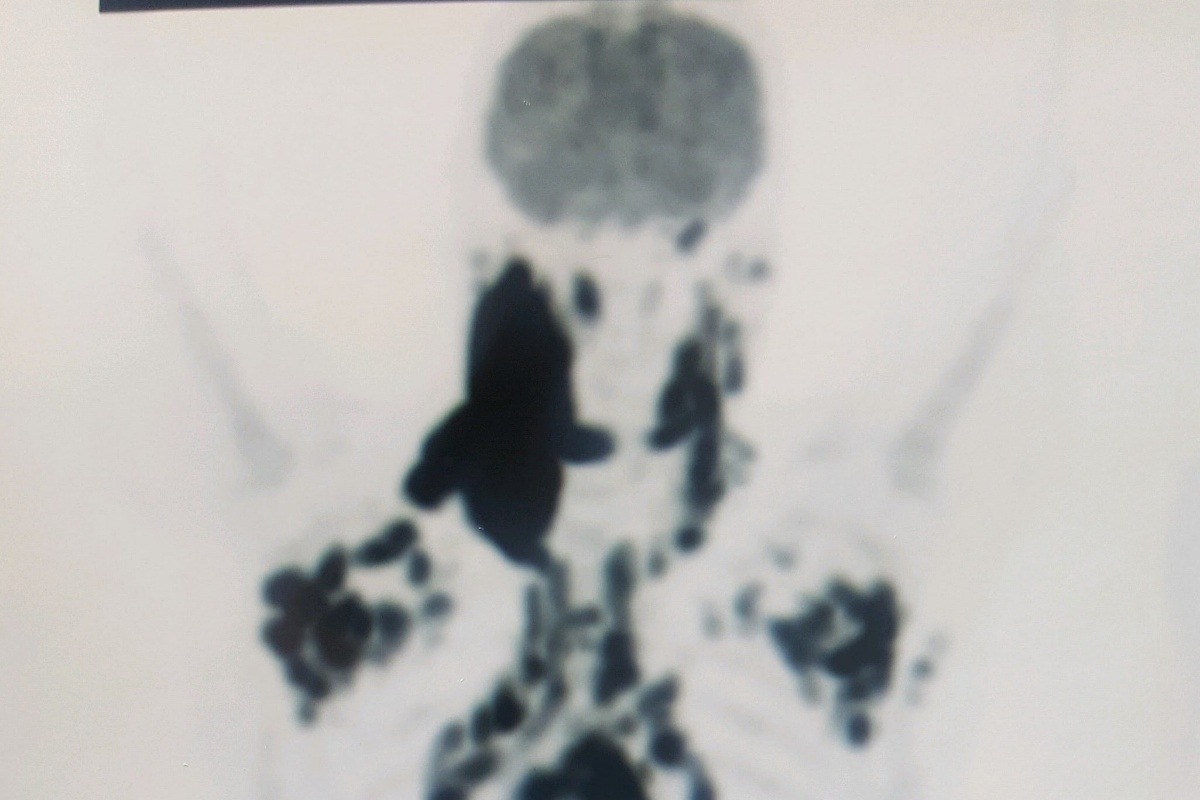

His PET scan, all the black color represents where the cancer has spread.

His PET scan, all the black color represents where the cancer has spread.